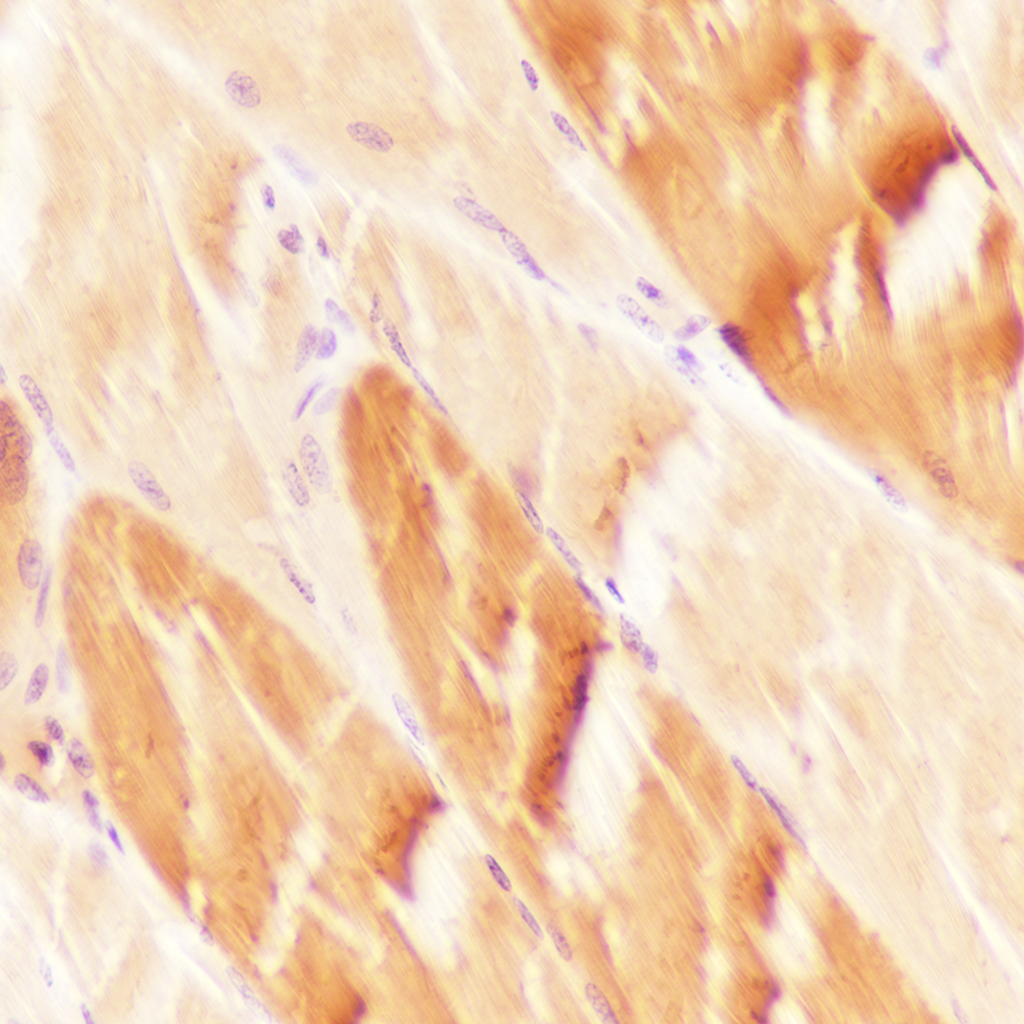

HSPB6 Monoclonal Antibody

Applications WB, IHC-P, IHC-F, IF

IHC-P IHC-P=1:100-500